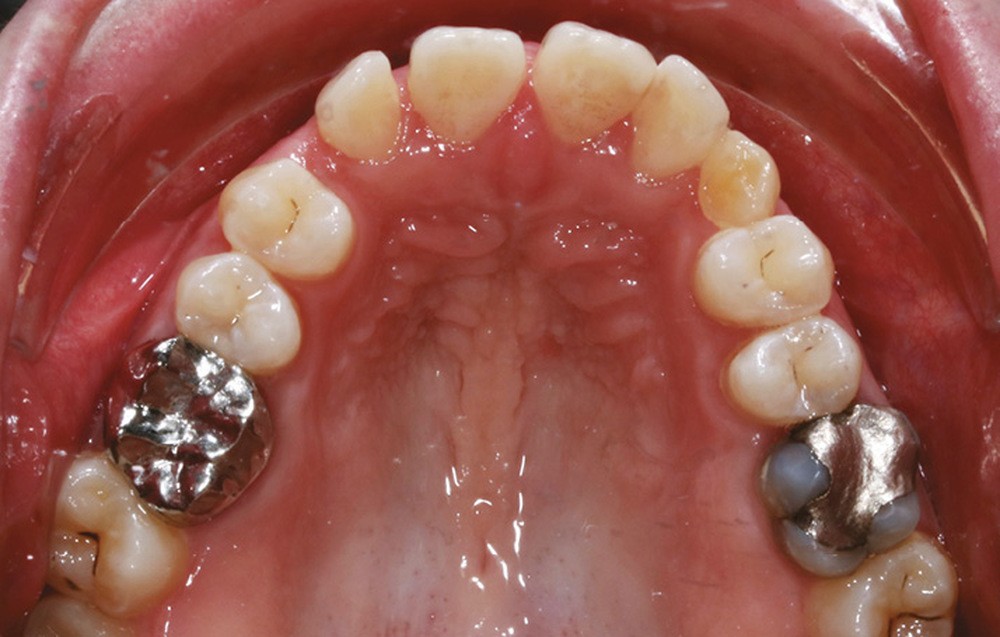

Sur le plan dentaire, on note l’absence des canines maxillaires permanentes sur l’arcade et la persistance de 63. Il existe une DDD par défaut maxillaire (indice de Bolton antérieur 90,2 %) due à l’absence des canines sur l’arcade, mais aussi à une dysharmonie de forme des dents maxillaires (fig. 2a-e).

L’examen radiologique 2D nous confirme l’inclusion de 13 et 23 en position haute, oblique en bas et en avant, couronnes en projection des apex de 11 et 21 et nous permet de quantifier le décalage squelettique (fig. 3 et 4). L‘examen radiologique 3D (cone beam) objective les rapports…